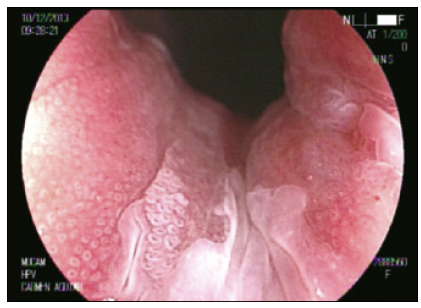

Cromoendoscopía digestiva magnificada en sustitución de la AAR convencional

La AAR en la literatura actual es sinónimo de colposcopía anal con tinción química.5, 7, 17, 18 Utilizando las nuevas tecnologías de la videoendoscopía digestiva es posible alcanzar una magnificación óptica de 200x, significativamente superior a la de un colposcopio de última generación. Nosotros trabajamos con una imagen magnificada de 100x que nos permite un mejor manejo del foco (Figuras 1 y 2).

El uso de capuchón es necesario al comienzo del entrenamiento. Con el advenimiento del sistema Laséreo, hemos sustituído la acetotinción por la cromotinción electrónica. Esto ha simplificado la técnica, acortando los plazos y las rotaciones del anoscopio, que pueden resultar molestas especialmente cuando hay hemorroides. El destaque de los cambios en el patrón vascular y glandular es igual de efectivo (Figura 3). El uso del colonoscopio permite valorar el recto, más allá del canal anal, con el fin de diagnosticar las metaplasias escamosas que pueden ser asiento de displasias VPH (Figura 4).